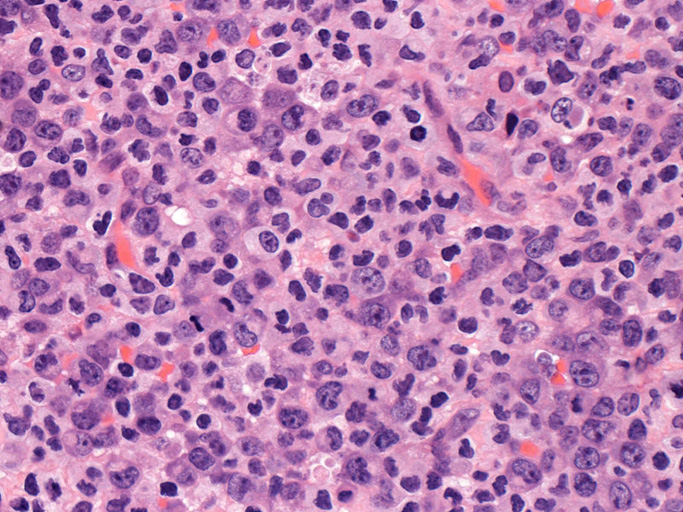

ALK/p80が細胞質・核に陽性となる。大型類円形核の細胞以外に, やや小型の類円形細胞に陽性細胞が認められるようです。背景細胞の多くはALK陰性。

ALKは核, 細胞質いずれにもびまん性に染まるパターンです。CD3, CD20は陰性でnull cellの様ですがCD45RO(UCHL-1)が膜に陽性となっています。